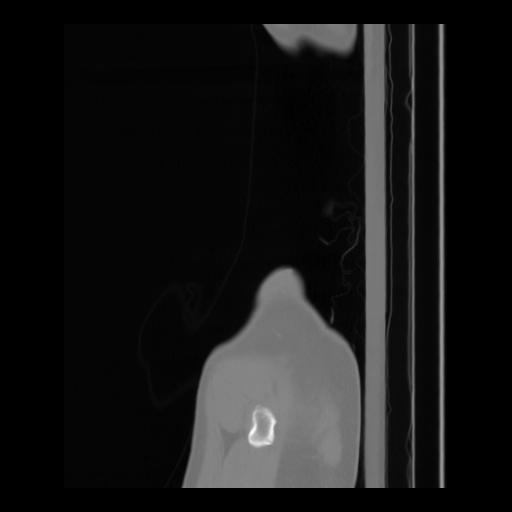

36 CUERPO,CE,Sagittal,3.000,CUERPO,Sagittal,